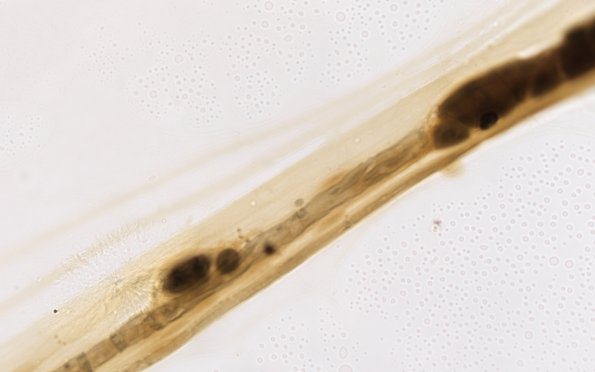

1A6,7 There is residual myelin debris in the demyelinated segment and disorganization of the adjacent node. (Teased fiber preparation)